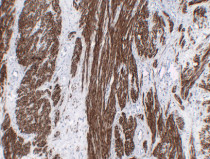

ARG66482 anti-Calponin 1 antibody IHC-P image

Immunohistochemistry: Paraffin-embedded Human fibroid stained with ARG66482 anti-Calponin 1 antibody at 1:200 (4°C, overnight). Antigen Retrieval: Citric acid buffer (pH 6.0) was used.